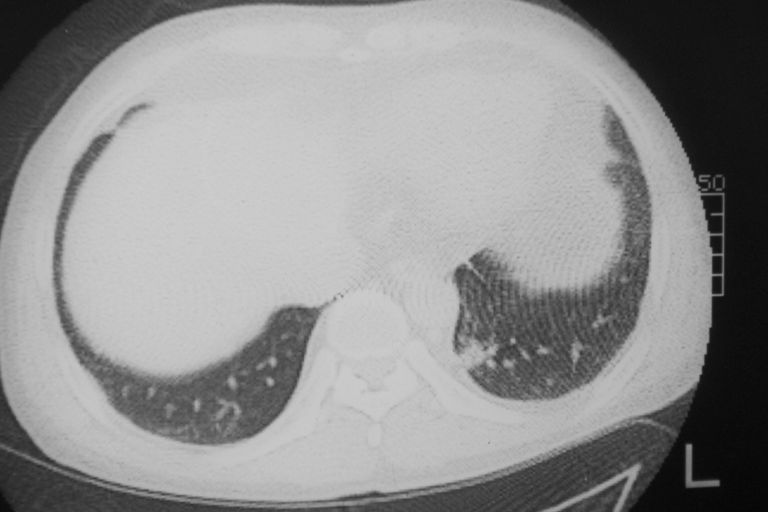

标题: CT10574:男 50岁胸部CT请会诊!

患者 男 50岁 无痛性咯血3天,无其他不适.

左下肺结节状软组织密度影,边缘有毛刺,考虑周围型肺癌。

1 左肺下叶基底段见两结节软组织密度灶, 肺窗边缘见有毛刺征像, 不能排除占位. 2 建议结合临床治疗一周后ct随访在看其结果.

临近胸膜增厚,病变周围肺不清,稍有分叶。结节密度略高,肺、纵隔窗差异不大,肺癌待排。前方还有一个

左下肺结节状软组织密度影,一个边缘有卫星病灶,邻近胸膜增厚.另一个有毛刺.心影周围水样密度影环绕.考虑:

1.肺癌可能.肺tb待排.

2.左侧胸膜增厚.心包积液.